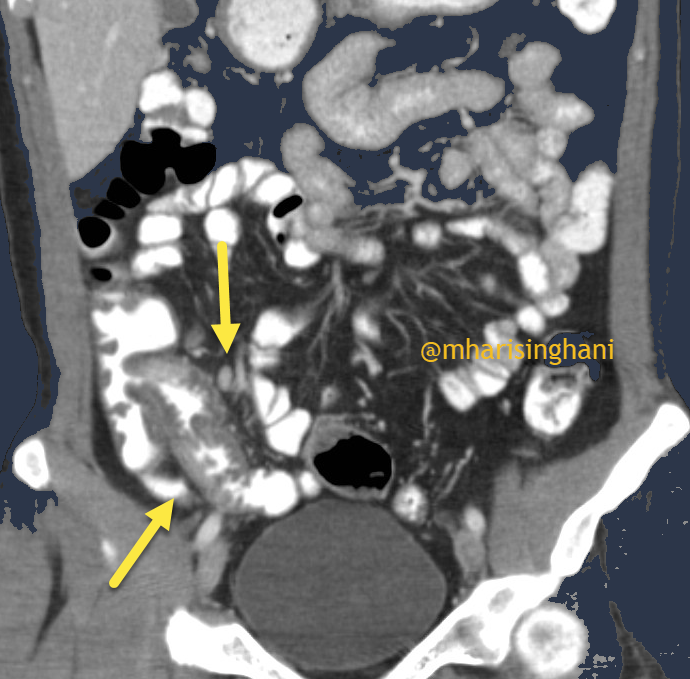

59 yo male with epigastric abdominal pain after eating meals x 2 weeks.

SMV thrombosis